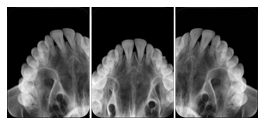

2 Occlusal Vertical Maxilla A Dental Image Layout

DL-C001A

Reference: DL-C001-U1L0

Reference: DL-C001-U2L0

00

Occlusal

18, 17, 16, 15, 14, 13, 12, 11, 13, 12, 11

01

21, 22, 23, 24, 25, 26,27, 28

2 Occlusal Horizontal Maxilla A Dental Image Layout

DL-C003A

Reference: DL-C003-U1L0

Reference: DL-C003-U2L0

18, 17, 16, 15, 14, 13, 12, 11, 13, 12, 11, 21, 22, 23, 24, 25, 26,27, 28